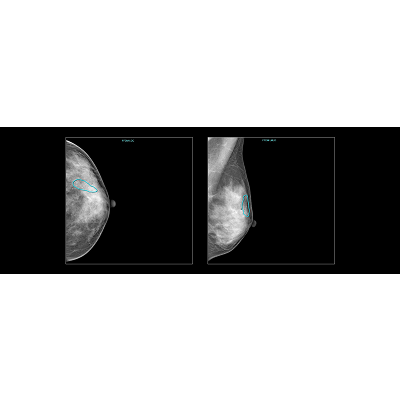

联影智能FFDM乳腺智能分析系统可辅助医生评估乳腺腺体分型及乳房内病灶的检出,包括乳腺常见的四大病灶:肿块、钙化、结构扭曲和不对称;同时系统提供病灶BI-RADS分类、定位等多维分析结果,自动生成图文报告,提升医生的阅片和工作效率,优化乳腺癌诊断流程,关爱女性健康。

基于AI技术,联影智能FFDM乳腺智能分析系统可对乳腺X线图像进行腺体分型、病灶检测及定位、多维分析病灶,避免不同医生阅片的主观差异,实现同质化水平,同时还能减轻医生阅片压力。